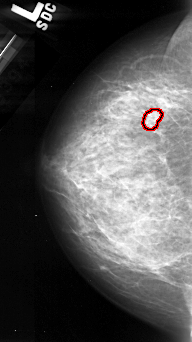

A_1097_1.RIGHT_CC

RIGHT_CC LINES 4291 PIXELS_PER_LINE 2461 BITS_PER_PIXEL 16 RESOLUTION 42 NON_OVERLAY

FILE: A_1097_1.LEFT_CC.OVERLAY

TOTAL_ABNORMALITIES 1

ABNORMALITY 1

LESION_TYPE CALCIFICATION TYPE PLEOMORPHIC DISTRIBUTION CLUSTERED

ASSESSMENT 4

SUBTLETY 4

PATHOLOGY MALIGNANT

TOTAL_OUTLINES 1

BOUNDARY